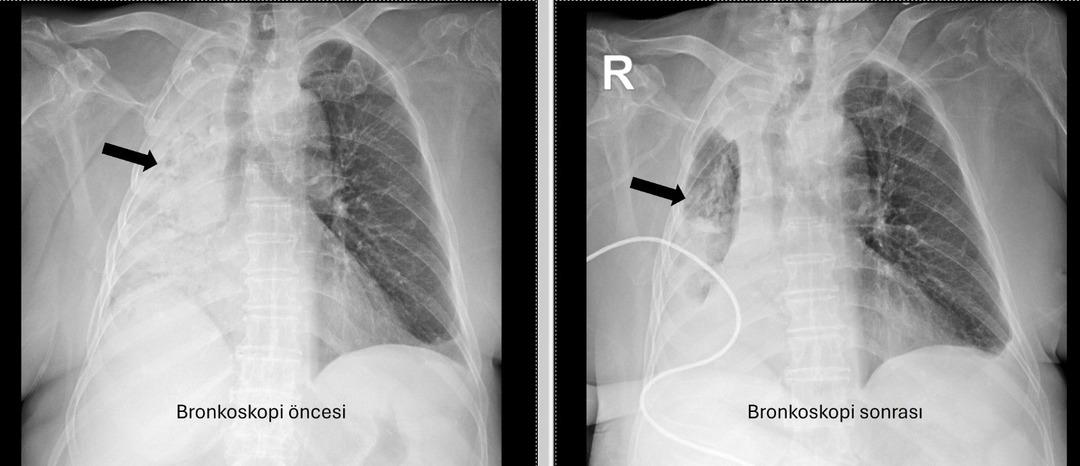

Pau Ökr Hastaneleri Göğüs Hastalıkları Bölümü. Prof.dr. Üye Dr.Köksel Altōiş Ergur, sağ akciğerler tarafından yapılan sınavlar için tamamen kapatıldı. Acil bronkoskopi planlandı ve prosedür derhal gerçekleştirildi. Dr. Al yaşşık ergur, hava yollarını incelerken çok yoğun ve karanlık bir salgılama ile esnek bir “bronkoskop” (esnek, katlanabilir), ancak hava yollarının derinlemesine temizlenmesini takiben, bir olaydan dolayı dönüştürüldüğünün, beraberinde bir şekilde dönüştürüldüğü ve beraberinde, bir olaydan dolayı dönüştürüldüğünü, berrak olduğunu, berrak olduğunu, berrak olduğunu açıkladığını, beraberinde kefil olduğunu açıkladığını açıkladığını açıkladığını açıkladığını açıkladığını açıkladığını açıkladığını açıkladığını açıkladığını açıkladığını, beraberinde getirdiğini açıkladığını açıkladığını açıkladığını açıkladı. Vücudun açık olduğu açık olduğu açık olduğu açık olduğu açıktı. genel anestezi ile yapılmıştır;

Prof. Alküzek Ergur, hastanın trakeasının nasıl engellendiğini açıkladı: “Havayollarında sıvı emen aspiratörün gücünü kullanarak nesneyi çıkarmak mümkün oldu. Hastanın hastanın tekrar yediği pizzada yediği pizza için daha önemli olduğu öğrenildi.